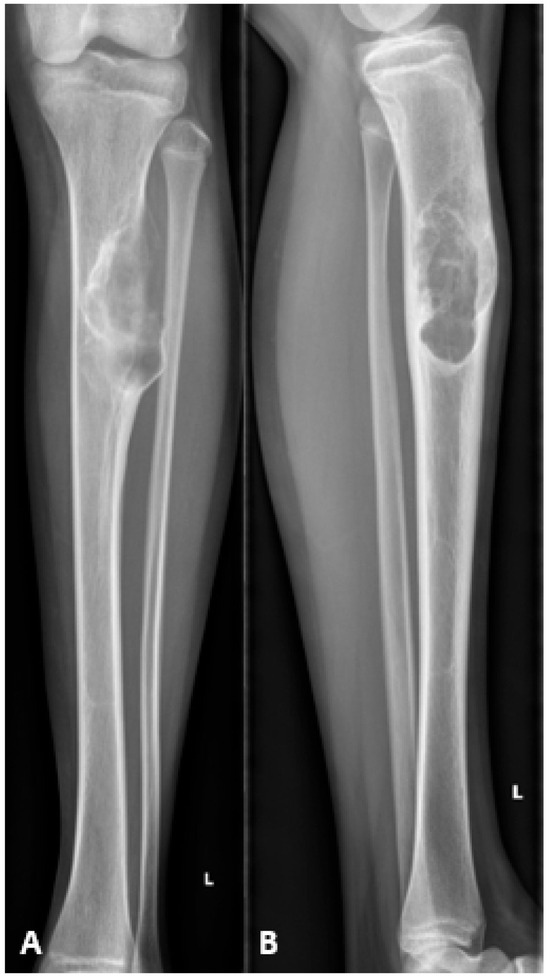

Background: Reconstructing large bone defects in pediatric patients after tumor resection is challenging, as conventional techniques are associated with high complication rates and morbidity. The Intramedullary Bone Transport Nail (IMBTN) may reduce these complications while preserving limb alignment and skeletal growth in pediatric oncologic reconstruction. Methods: A 15-year-old female with an osteofibrous dysplasia-like adamantinoma of the tibial diaphysis underwent complete en-bloc resection, leaving a 9 cm bone defect. An IMBTN (Precice, NuVasive) was implanted for distraction osteogenesis, with distraction starting eight days post-surgery at 0.25 mm twice daily. Follow-up visits monitored bone healing, alignment, and limb length. Results: The 9 cm defect was successfully reconstructed, with complete bone healing at the distraction site. Complete consolidation was confirmed at 18 months. The transport nail was removed at two years, and no further revisions were necessary. At two-year follow-up, the patient reported minimal pain on the Visual Analog Scale 1/10, and no recurrence of the tumor was noted. Conclusions: The use of IMBTN for large bone defect reconstruction following tumor resection in pediatric patients is a safe and effective technique. It enables stable bone transport while preserving alignment, maintaining limb length, and is less invasive than traditional reconstructive approaches. Full article

Figure 1